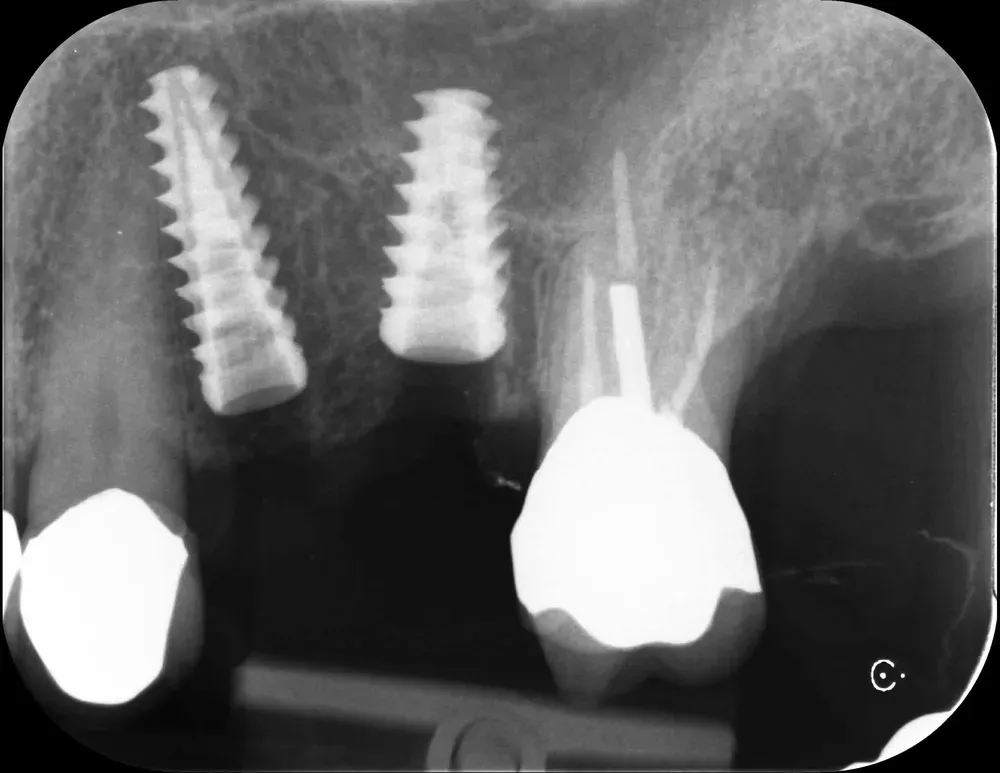

Di seguito, le radiografie periapicali mostrano gli impianti appena inseriti e gli abutment con i provvisori.

Rx Periapicale Post-op

Rx Periapicale con abutment e provvisori

Passati tre mesi, abbiamo effettuato una scansione per realizzare le corone in zirconia. L’ultima radiografia è stata scattata il giorno della consegna delle corone.

L’aumento della densità ossea intorno all’apice dell’impianto in posizione 2.5 è evidente, particolarmente in zona mesiale. In quella zona, la corticale del seno si è sollevata maggiormente.

Rx periapicale alla consegna delle corone in zirconia